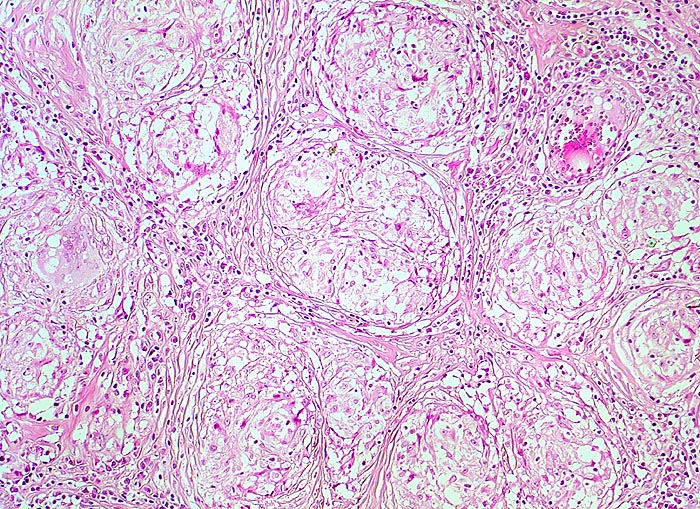

Sarkoidosegranulome bestehen aus Epitheloidzellen mit einem peripheren Lymphozytensaum. Mehrkernige Riesenzellen, meistens solche vom Langhans-Typ mit hufeisenförmig angeordneten Kernen und Asteroidkörperchen (> 4173) können zusätzlich vorhanden sein. Diese Granulome enthalten meist keine Nekroseherde (=produktives Granulom). Man findet diesen Granulomtyp hauptsächlich in Lymphknoten, aber auch in inneren Organen und in der Haut. Die Sarkoidosegranulome zeigen in späteren Stadien eine charakteristische perigranulomatöse und die Granulome septierend unterteilende Fibrose (> 4015).

Morphologische Merkmale:

• Wenig erhaltenes Lymphknotengewebe (blau).

• Konfluierende Granulome aus grossleibigen Epitheloidzellen.

• Wenige mehrkernige Riesenzellen.

• Kleinere Nekroseareale im Zentrum grösserer Granulome. (Die Nekrosen sind untypisch für die Sarkoidose, können aber bei grossen Granulomen gelegentlich vorkommen).

• Perigranulomatöse Fibrose. Das sollte der Kliniker dem Pathologen mitteilen: